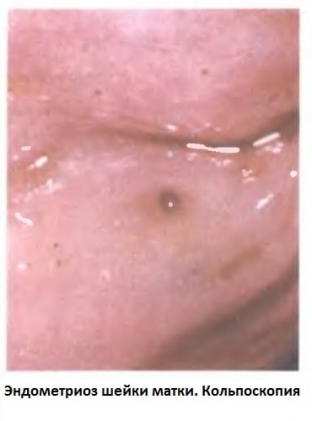

An important role in the diagnostic process of endometriosis of the cervix is ​​played by a routine gynecological examination of the cervix in the mirrors. During this study, endometriotic lesions are visualized as nodular or fine-grained lesions on the mucous membrane of the cervix, dark purple or red.

kakie-metody-pomogut-raspoznat-endometrioz-shejki-matki Lesions can enlarge significantly during menstrual bleeding, in some cases they open up and empty. After menstruation, the foci of endometriosis decrease in size and become pale. An important diagnostic study is colposcopy and cervicoscopy, which allows diagnosing paracervical extension of endometriosis in the presence of lateral mucosal defects.